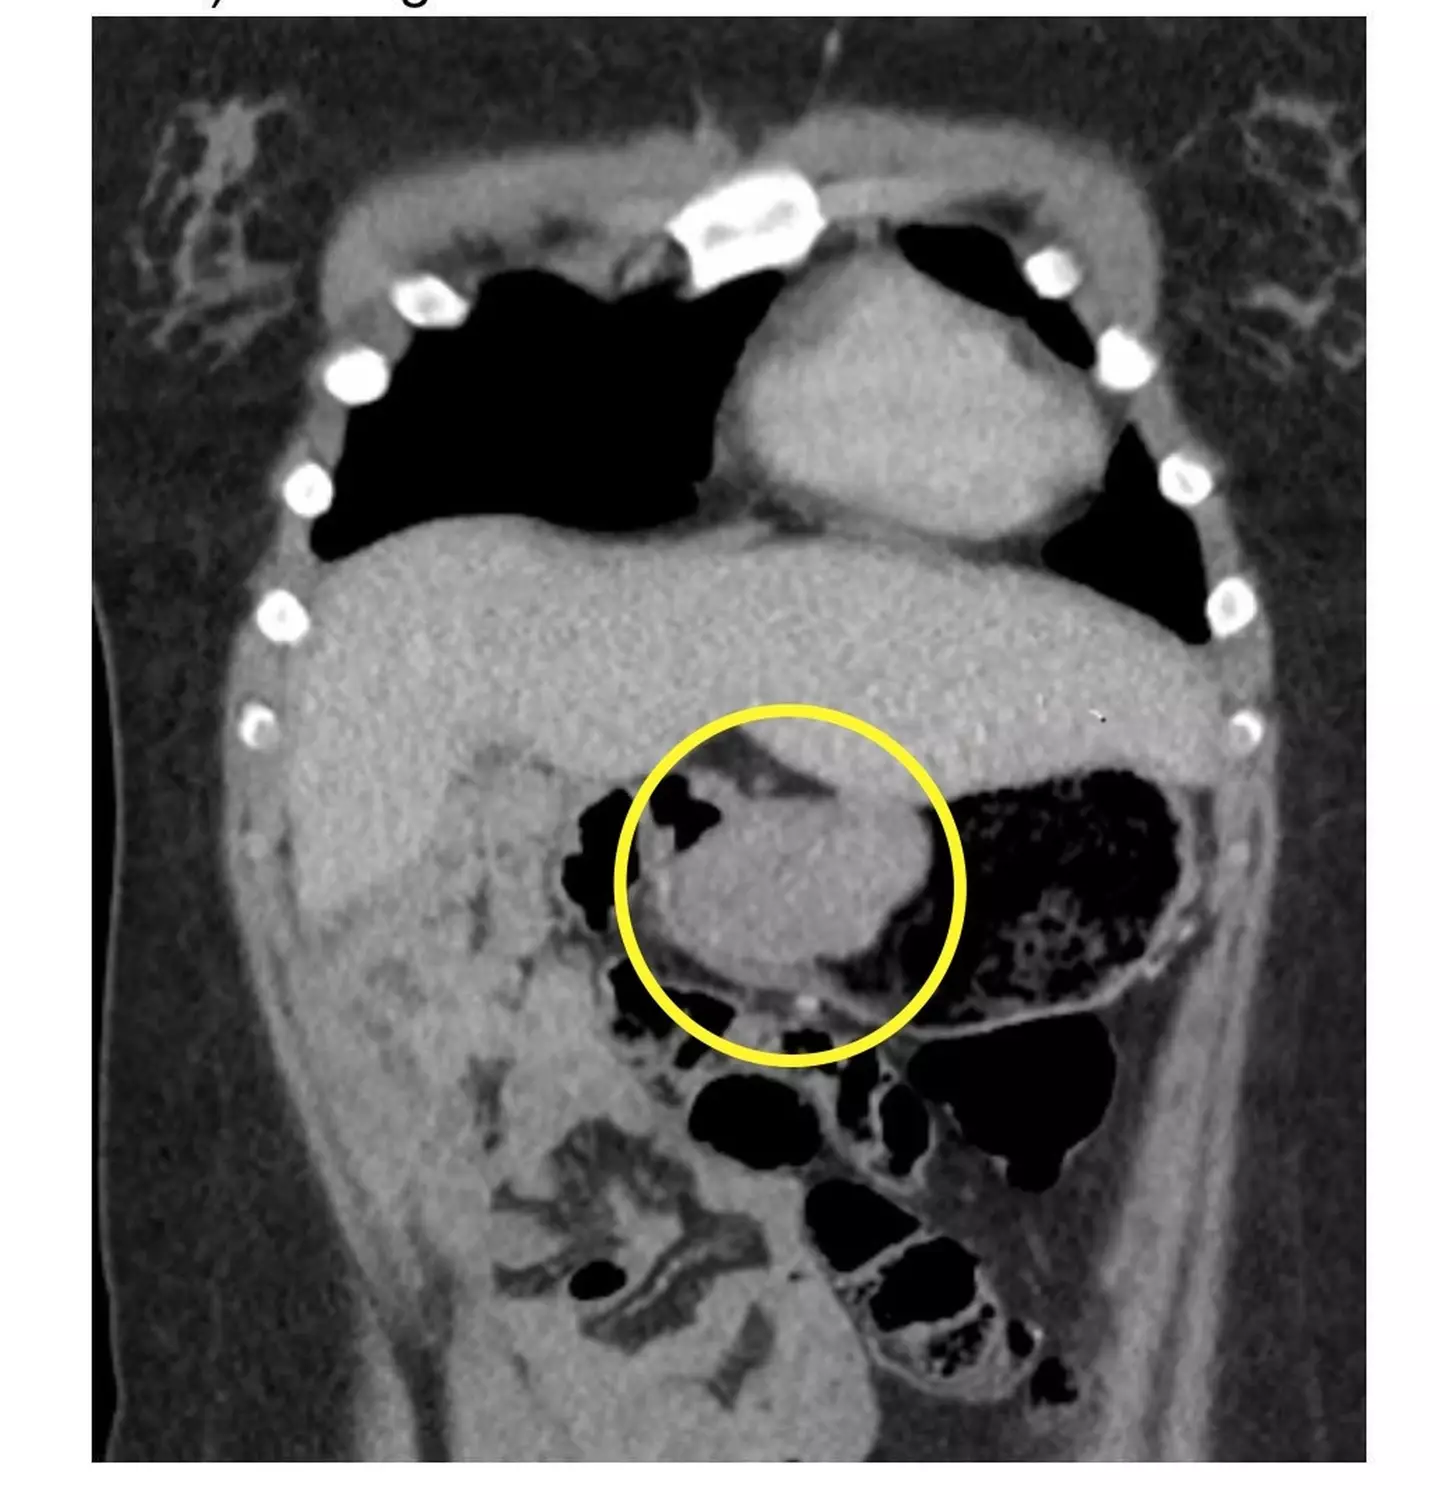

A six-centimeter tumour was found in Bella’s stomach, revealing she had a gastro-intestinal stromal tumour (GIST). This is a rare form of cancer caused by a sarcoma developing in the digestive system.